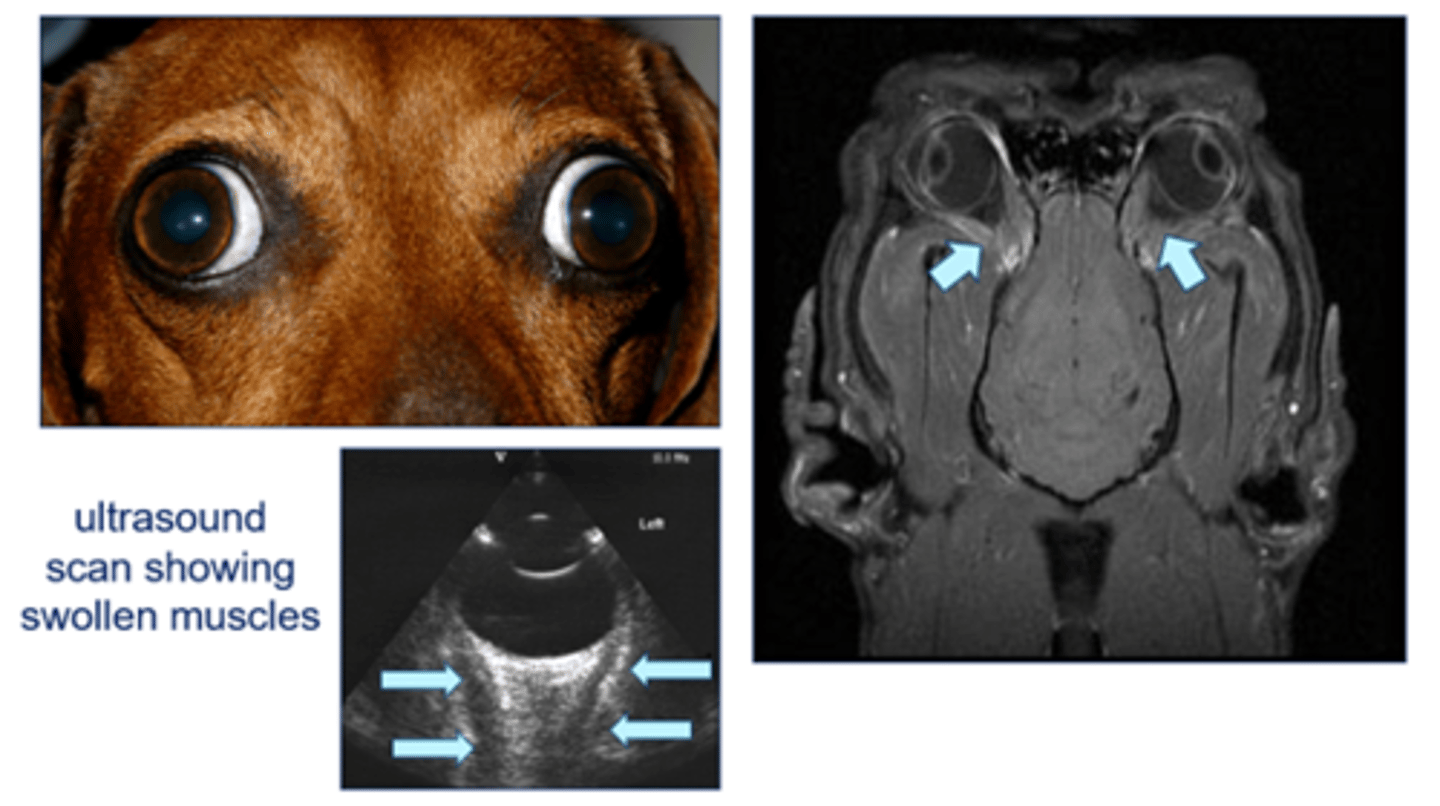

Dachshund with extraocular polymyositis (muscles around eye are swollen and inflamed)